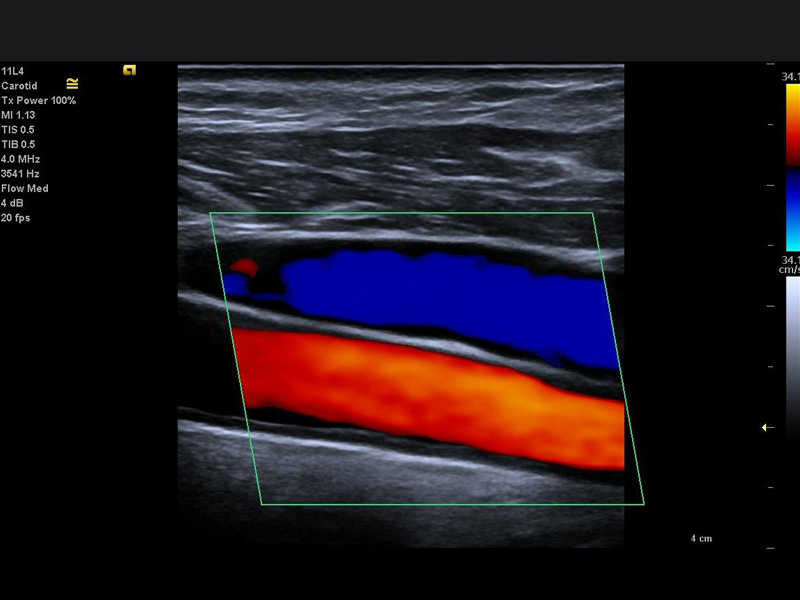

Dentre os exames de ultrassonografia, os exames Doppler se caracterizam por avaliar de forma específica detalhes do sistema circulatório, de forma não invasiva, ou seja, sem uso de medicamentos, meios de contraste, sem uso de radiação, e sem necessidade de sedação ou internação hospitalar, de forma indolor e sem efeitos colaterais, podendo ser realizado inclusive em gestantes para avaliação do bem estar do feto. Um dos principais benefícios dos exames Doppler é justamente a avaliação da saúde fetal, quando o médico examina principalmente as artérias do cérebro fetal, do cordão umbilical e também as artérias uterinas. Com base nos dados obtidos, é possível prever, por exemplo, a chançe da gestante desenvolver hipertensão gestacional, bem como se o feto está recebendo pelo cordão umbilical a oxigenação necessária, ou se há algum sinal sugestivo de redução da oxigenação cerebral. Algumas vezes pode ser preciso, caso a circulação fetal esteja muito comprometida, realizar o parto antes da data prevista, e o exame Doppler obstétrico é fundamental para auxiliar na decisão da melhor hora para a intervenção do médico obstetra. Nas áreas de cardiologia, neurologia e cirurgia vascular, a aplicação do exame Doppler é ampla. Os exames mais realizados são o Doppler de carótidas e vertebrais (artérias da região do pescoço que cursam para o cérebro), e o doppler de membros inferiores, tanto para avaliação de trombose, varizes e redução da circulação arterial. Nesses casos, o exame auxilia o médico assistente na análise de placas ateromatosas (depósitos de colesterol e calcificações), bem como se o fluxo sanguíneo está suficiente ou insuficiente para os órgãos específicos, ou ainda se há alguma trombose venosa ou oclusão das artérias. No caso das varizes, o exame detalha a anatomia venosa, bem como onde a causa das veias dilatadas se inicia, as veias insuficientes, o trajeto varicoso, e é fundamental para o planejamento e escolha da técnica cirúrgica, reduzindo de forma significativa o índice de recidivas e complicações pós-operatórias. O exame Doppler é também realizado na diferenciação de lesões de outros órgãos, como na tireóide e na mama, e tem grande importância na avaliação de órgãos pré e pós transplantes, como por exemplo do fígado e dos rins.